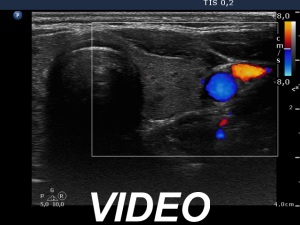

Ultrasonography. The thyroid was echonormal. There were several small, moderately hypoechogenic lesions and a larger, minimally hypoechogenic nodule in the right lobe. The latter was composed of smaller areas. The left thyroid contained moderately hypoechogenic small areas.